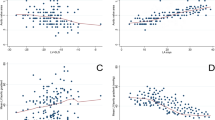

To find out the ideal LV-GLS cut-off value for predicting the AVS, ROC analysis was performed. A LV-GLS value of > − 18 has 85.8% sensitivity, 67.5% specificity for the prediction of the AVS [AUC 0.754, (p < 0.001)] (Fig. 2).